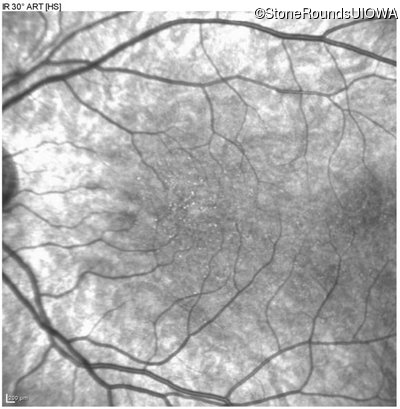

Infrared Fundus Photograph - Right - 20/40 sc

Exemplar